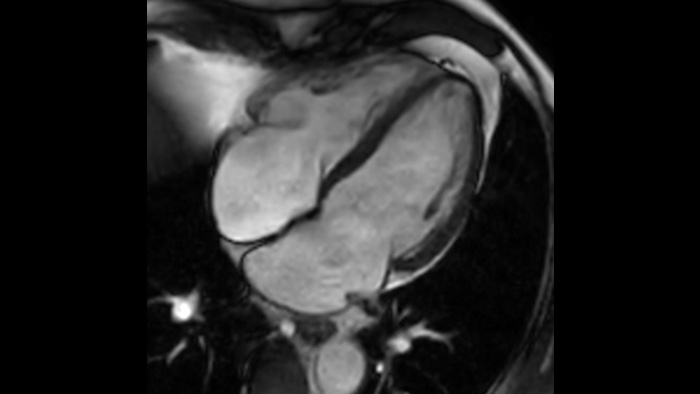

Speed & Comfort Provide up to 40% reduction in breath holds, with virtually equal image quality4.

Learn how MCVI boosts MRI quality.

Diagnostic confidence Expand your imaging capabilities in all clinical areas. See how your peers are benefiting.